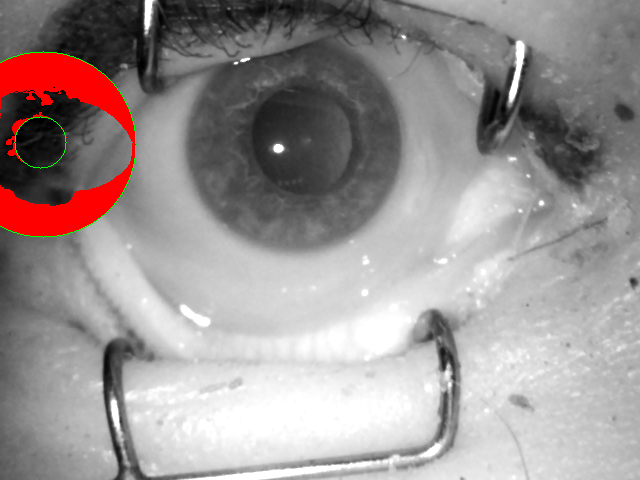

During data acquisition, we had the opportunity to collect images using two types of cameras: one producing near-infrared images of VGA size ( pixels), and the second producing color photographs of high resolution. Both near-infrared and visible-light images were used in visual inspection presented in Sec. IV-B. Using only red channel of color iris samples acquired in visible-light has been found to offer high recognition accuracy [31] even when being matched with near-infrared samples [32]. Thus, in this study, two types of samples are used: a) original near-infrared and compliant to ISO/IEC 19794-6 and ISO/IEC 29794-6 standards, and b) red channel of visible-light images manually center-cropped to conform the VGA image type, as defined in ISO/IEC 19794-6. Hence, the resolution of all images is pixels. This cropping of visible-light sample additionally protects the identity of donors, as original high-resolution visible-light images contained significant portions of face region. An example pair of near-infrared sample and the cropped red-channel image of the same eye is shown in Fig. 4.

V-B2 Manually-annotated ground-truth iris masks

The erroneous execution of the segmentation stage is usually a main cause of drops in iris recognition performance, when samples presented to the algorithms are of challenging nature. To test whether this is also the case for post-mortem data, we have taken the effort to prepare manually annotated iris masks for all of the iris images involved in this study, including both NIR and visible light samples, as depicted in Fig. 4.